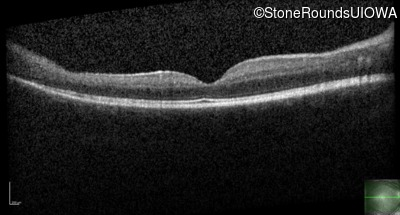

Optical Coherence Tomography - Right - 20/32

Exemplar / OCT Stack